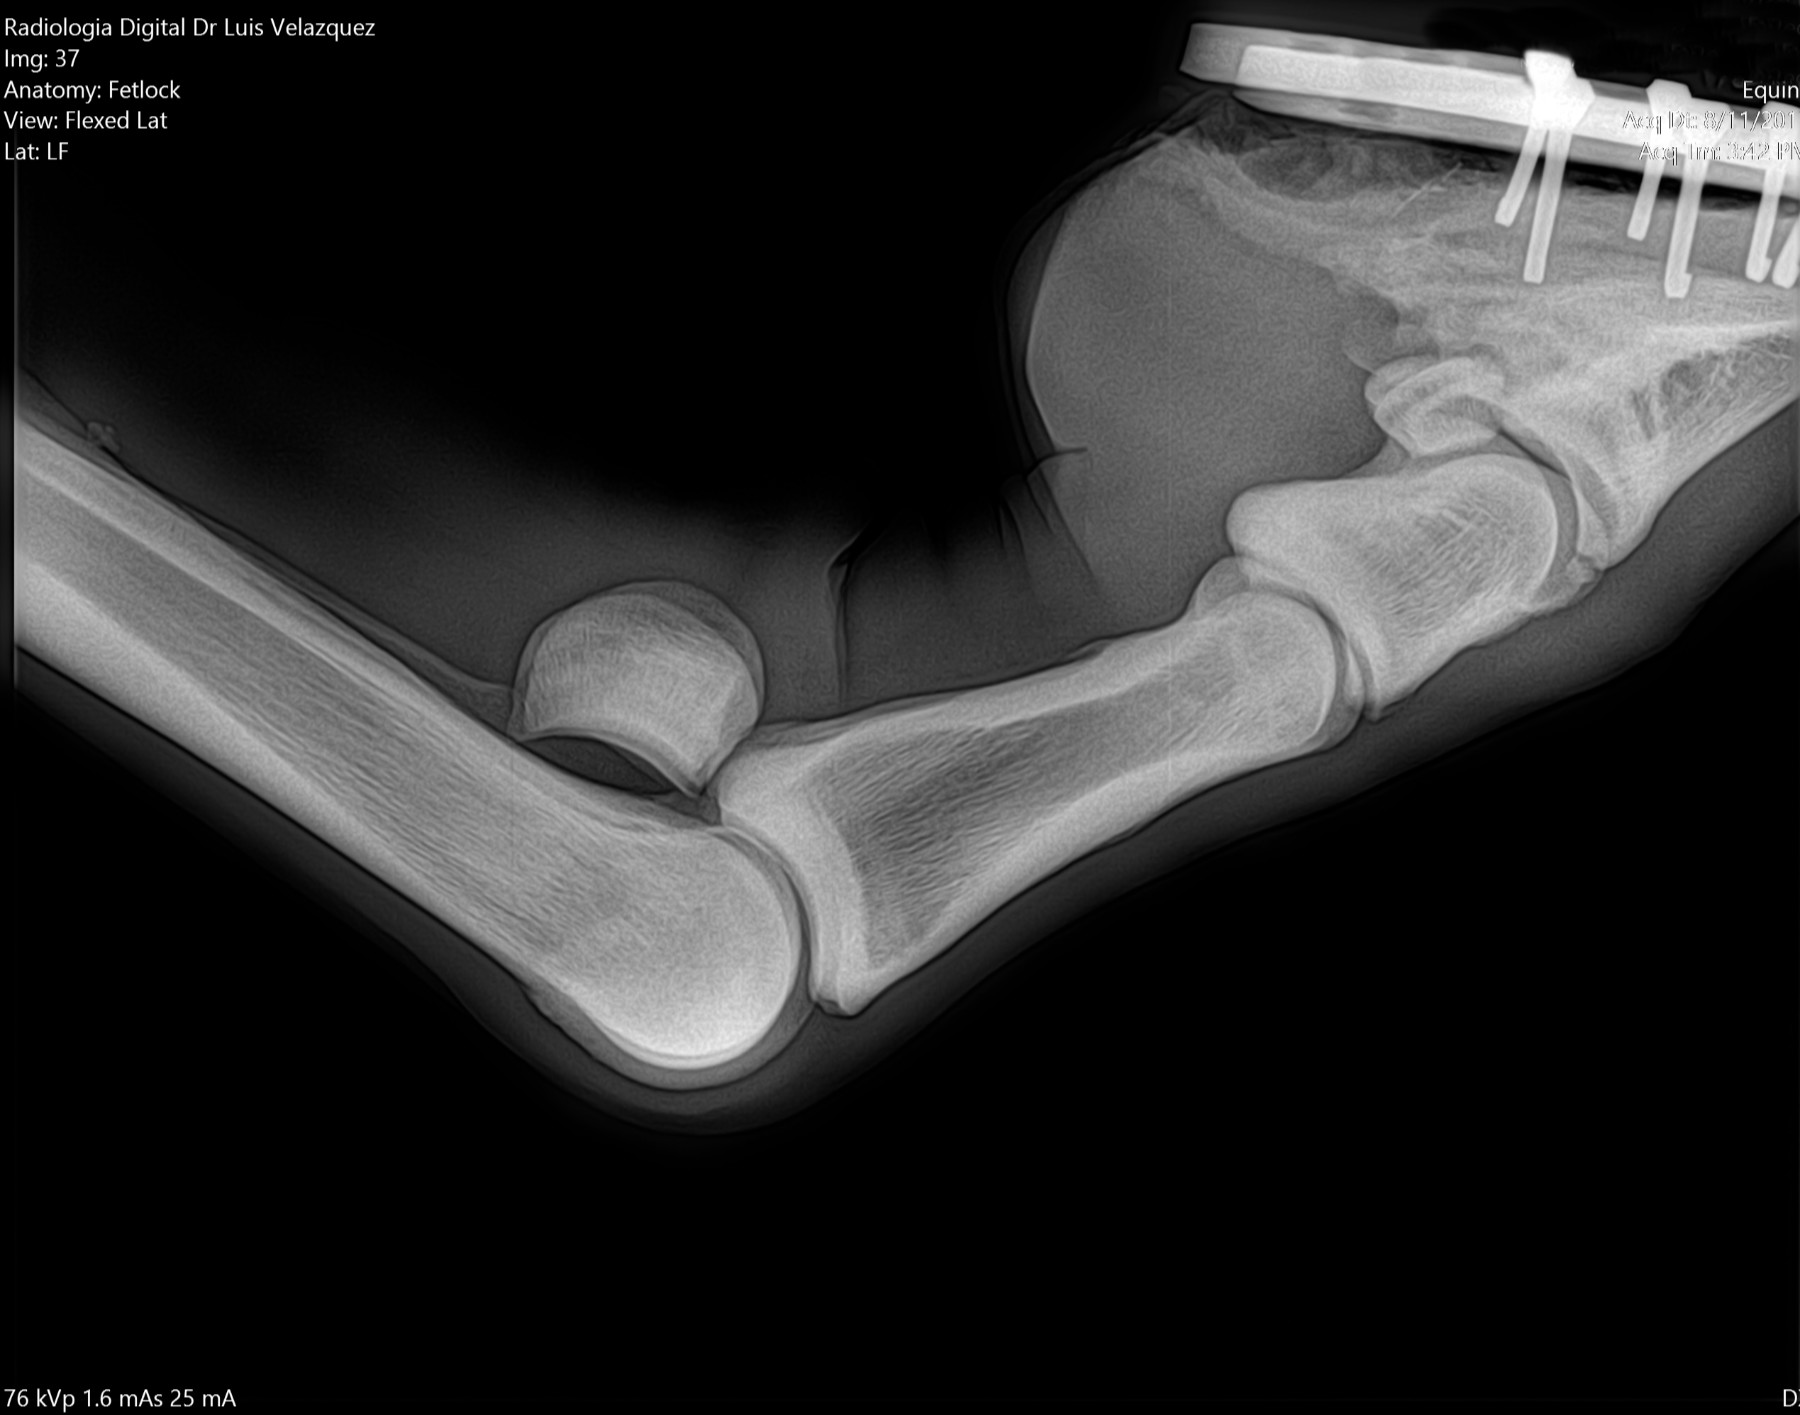

Radiología Digital como Herramienta Complementaria en el Dictamen de Bienes Muebles

Cambios Térmicos en las Extremidades de Caballos,

Asociados a Golpes y su Evaluación por Termografía.

Los caballos de salto, en competencia, pueden derribar obstáculos y lastimarse. Si se golpean, no siempre claudican. Considerando al calor como un signo de inflamación, se evaluaron los cambios térmicos de 6 áreas de las extremidades torácicas y pelvianas de 23 caballos de salto en nivel de competencia de 1.05 a 1.60 m de altura, por medio de termografía durante 4 días de competencia (N=2208 áreas).